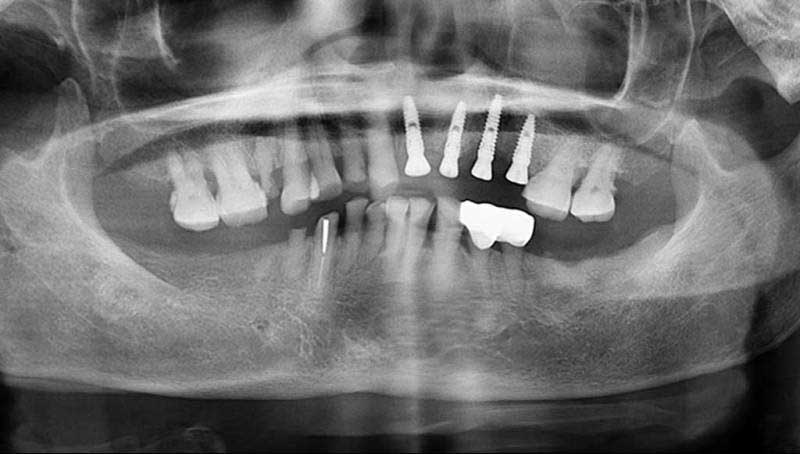

案例2